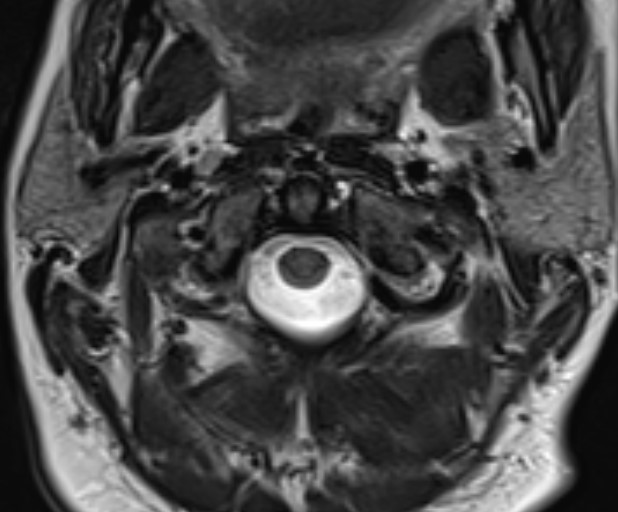

MRI

Assess transverse ligament

Assess space available for cord (SAC)

Intact transverse ligament on MRI